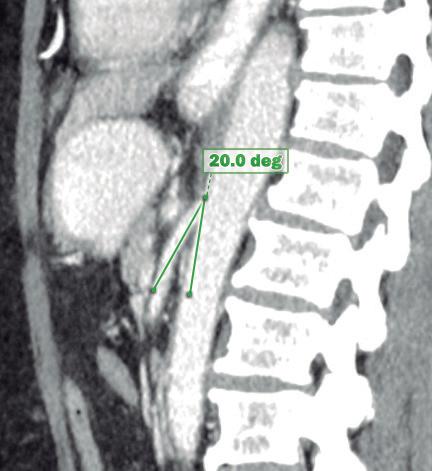

Paciente con vómitos en el periodo posoperatorio

Germán Francisco Rojas, Gabriel Adrián Mariño Camacho, Jesica Antonella Andruetto, Martín José Drago, Alejandro Moreira Grecco, Mariano Volpacchio, Esteban González Ballerga

Patient with Postoperative Vomiting